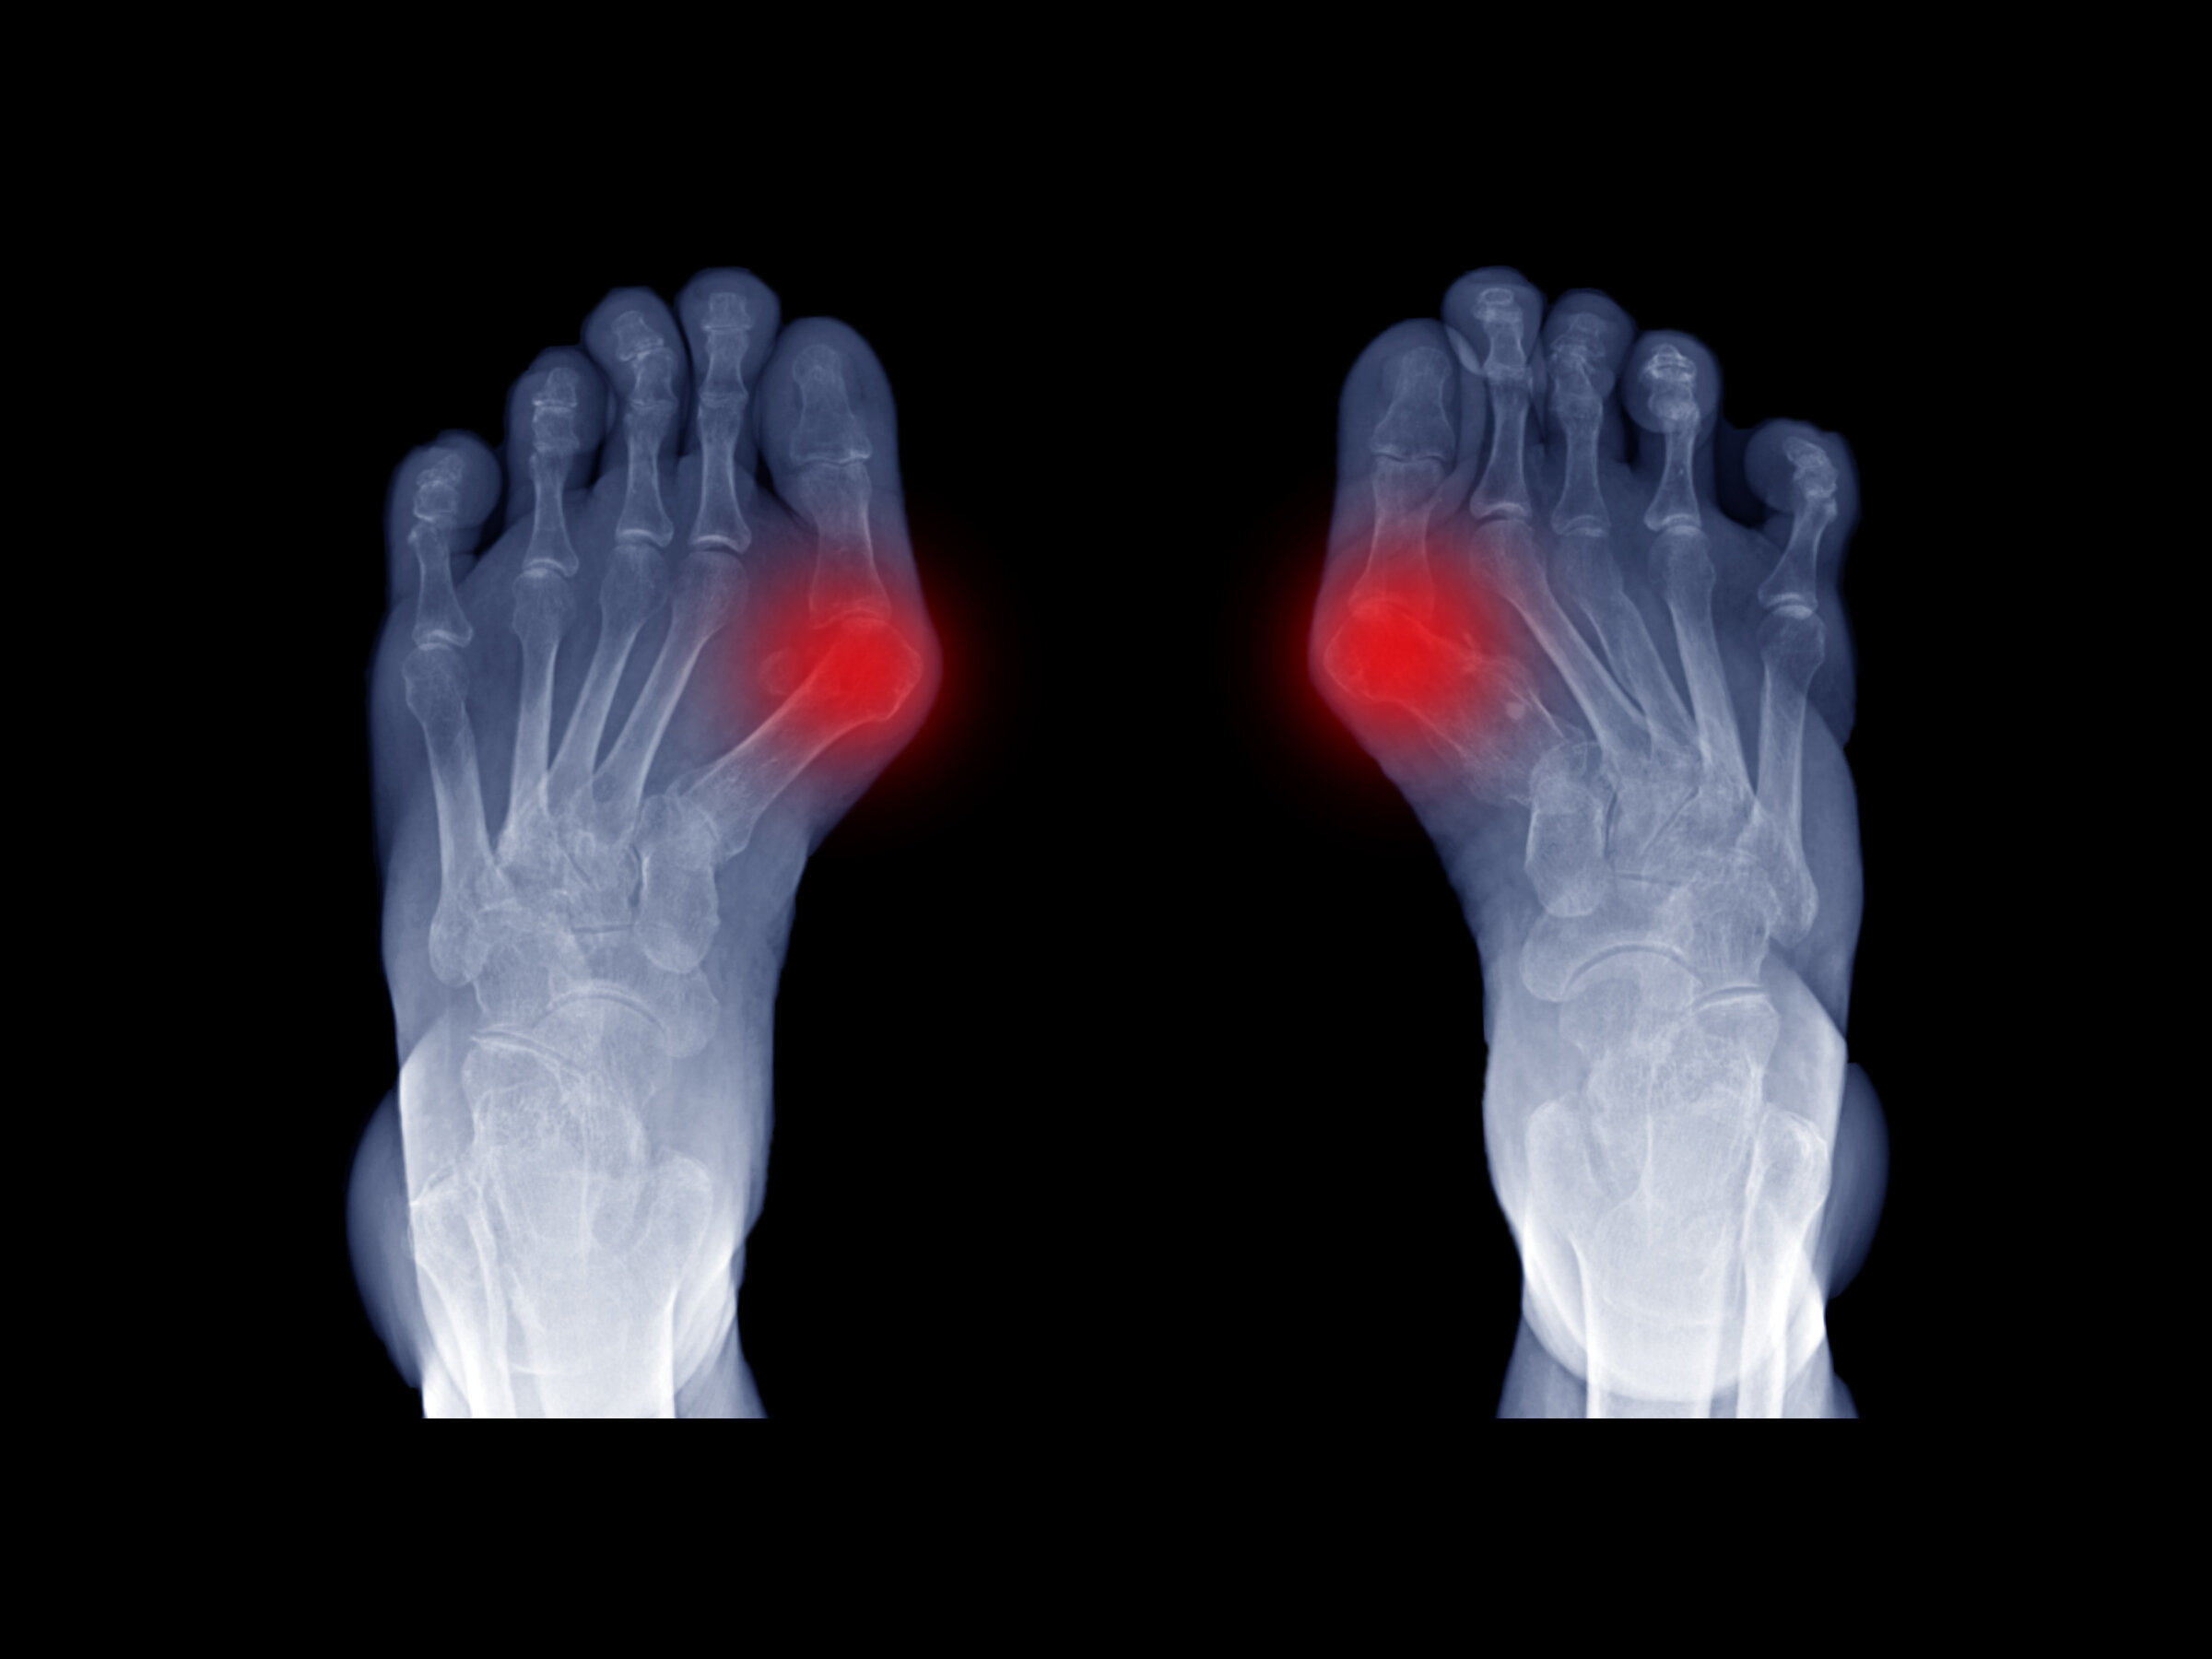

Bunions can be painful. When they progress to the point where it’s difficult to do your favorite activities, it’s time to seek treatment.